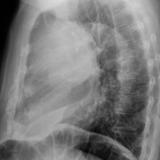

Case 1c

Thymoma

Date: 03/17/2004

Views: 4708